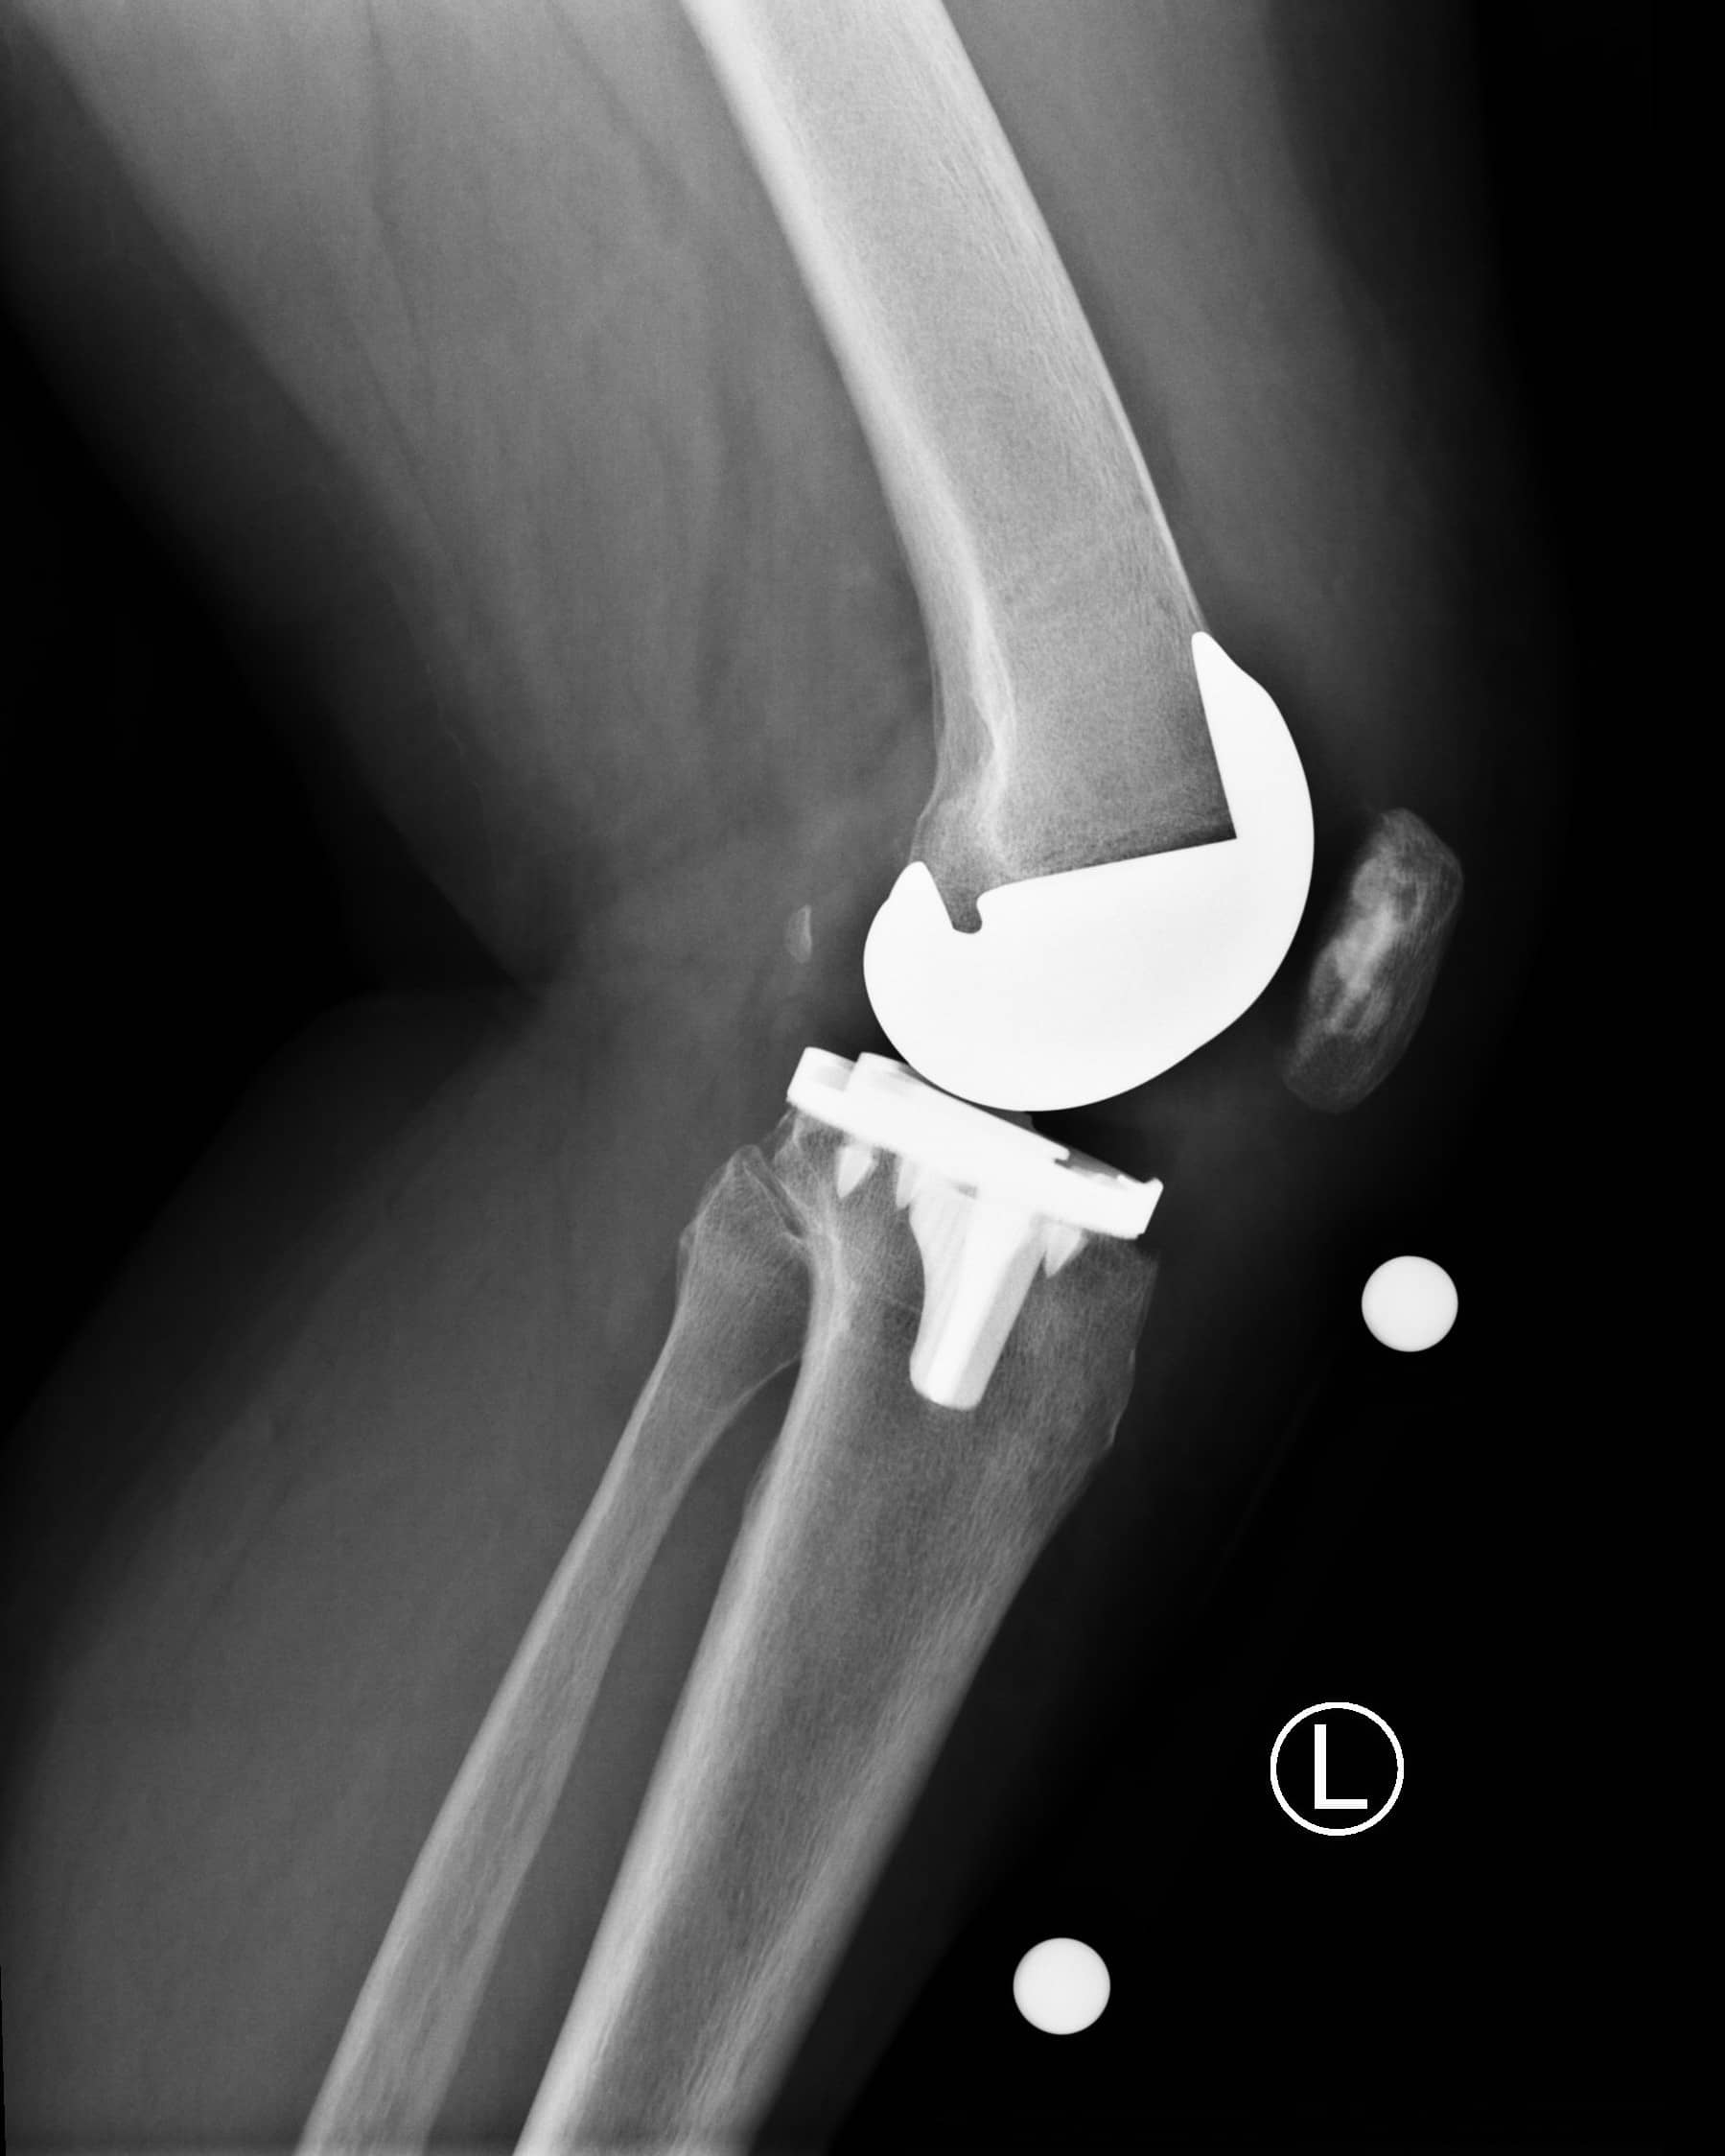

Mako Robotic Total Knee Replacement Reviews . Was just wondering what other people's thoughts. In the operating room, your surgeon guides mako’s robotic arm to remove arthritic bone and cartilage from the knee. I had my first mako left tkr in 5/2018 and the right is planned for 10/22/19. Mako’s accustop™ technology creates a virtual boundary that provides.